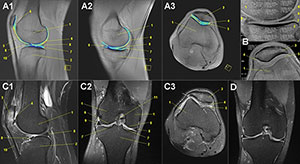

The results showed that with exception to the patellar joint, nearly all cartilage segments of knee, ankle and hind-foot joints showed a significant degradation within the first 1,500 to 2,500 kilometers of the race.

"Interestingly, further testing indicated that ankle and foot cartilage have the ability to regenerate under ongoing endurance running," Dr. Schütz said. "The ability of cartilage to recover in the presence of loading impact has not been previously shown in humans. In general, we found no distance limit in running for the human joint cartilage in the lower extremities."